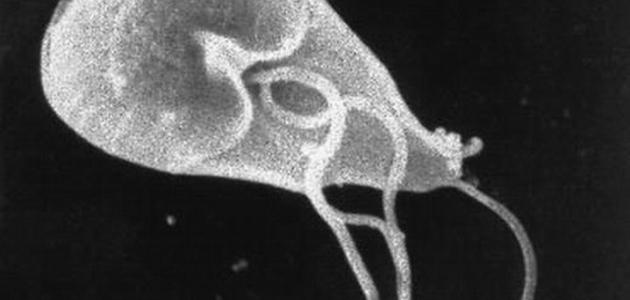

ما هي طفيليات الجيارديا وما أعراض الإصابة بها؟

عمون - طفيليات الجيارديا هي طفيليات مجهرية تسبب الإصابة بالتهاب الأمعاء، وتعتبر الأنواع الأكثر شيوعًا للجيارديا في البشر هي Giardia lamblia. تنتشر هذه الطفيلية عادةً من خلال استهلاك الماء الملوث أو الأطعمة الملوثة بالبراز المصاب بالطفيلية. وتعيش الجيارديا في الأمعاء الدقيقة للإنسان وتستخدمها كمستضيف لتكاثرها والاستفادة من المواد الغذائية المتوفرة في الأمعاء.